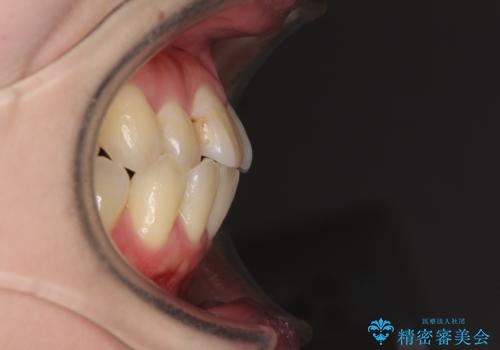

- 下顎の歯が舌側に倒れていることと、前歯の咬み合わせの不具合を気にして来院された患者様です。

受け口傾向の口元であるため、下顎左右小臼歯各1歯を抜歯して歯列を整えることとしました。